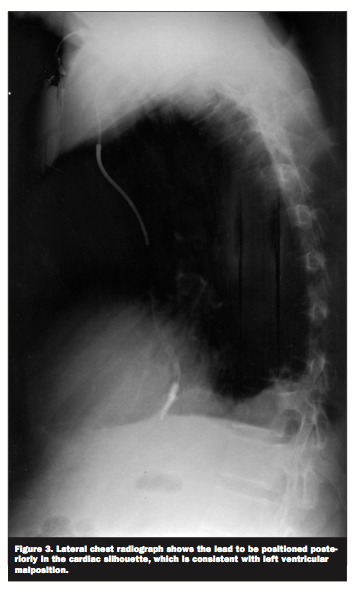

A 50-year-old male with congestive heart failure secondary to Ebstein’s anomaly presented for recurrent shocks from his implantable cardioverter-defibrillator (ICD). His electrocardiogram (ECG) (Figure 1) showed paced rhythm with right bundle branch block morphology which raised the question of left ventricular malposition of the ICD lead. On the postero-anterior chest radiograph (Figure 2) the tip of the lead was situated very far laterally to the left sternal border. A lateral chest

radiograph (Figure 3) showed the lead to be positioned posteriorly in the cardiac silhouette, which is consistent with left ventricular malposition. Subsequent echocardiography (Figure 4) showed the lead to be passing through the atrial septal defect and across the mitral valve into the left ventricle.

atrial or ventricular septal defects.1,2 It can cause thromboembolic events like stroke or peripheral arterial occlusion. This complication can be easily missed on intraoperative fluoroscopic imaging. ECG and chest radiographic findings often suggest the diagnosis. In proper positioning, the tip of the lead is expected to be adjacent to the left sternal border on the postero-anterior radiograph and to run anteriorly in the cardiac silhouette on the lateral radiograph. Definitive diagnosis can be established via echocardiography.